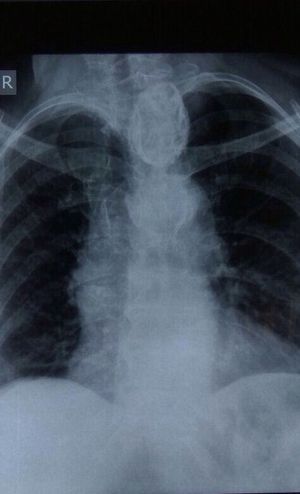

X ray of a female patient having mild cardiomegaly and retrosternal thyroidism

I had never seen such a CXR